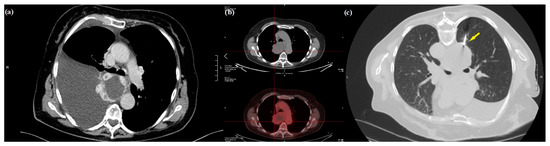

2. Case Presentation